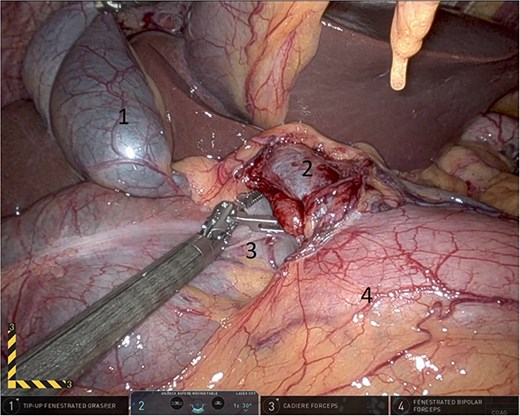

Upon entering the abdominal cavity, dilated bowel loops were observed (Fig. 2), and a significant portion of the colon was found herniated through the foramen of Winslow (Fig. 3). The herniated colon was covered by the pars flaccida (Fig. 4) (Video S1). Careful dissection was performed anterior to the hepatoduodenal ligament (Fig. 5). The gall bladder was retracted to the patient's right upper quadrant, which allowed for the retraction of the foramen of Winslow (Fig. 6) (Video S1). After carefully placing the tip of the instrument posterior to the portal vein and gently elevating it, the herniated colon was successfully reduced (Fig. 7) (Video S1).

Dissection anterior to the hepatoduodenal ligament (1: portal vein, 2: foramen of Winslow, 3:first part of the duodenum).

Gallbladder was retracted to the patient's right upper quadrant which allowed for the retraction of the foramen of Winslow and anterior mobilization of it (1: gall bladder, 2: herniating colon, 3: first part of the duodenum, 4: portal vein).